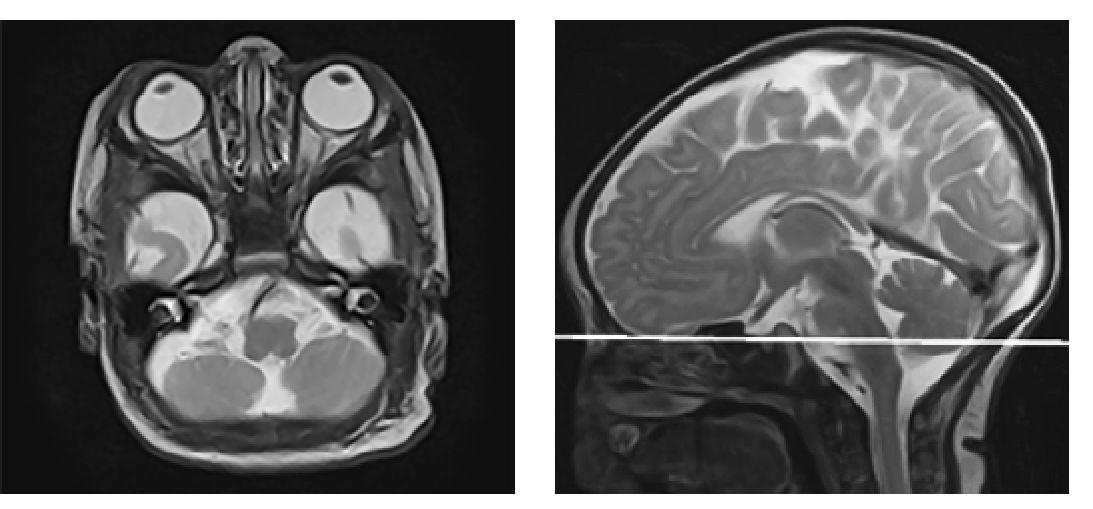

1. Аксиальная проекция - по орбитомеатальной линии (рис.1).

Рис. 1. Пример позиционирования срезов по орбитомеатальной линии в сагиттальной плоскости для получения изображения в аксиальной проекции при проведении магнитно-резонансной томографии головного мозга на примере Т2 ВИ пациенту восьми месяцев жизни.